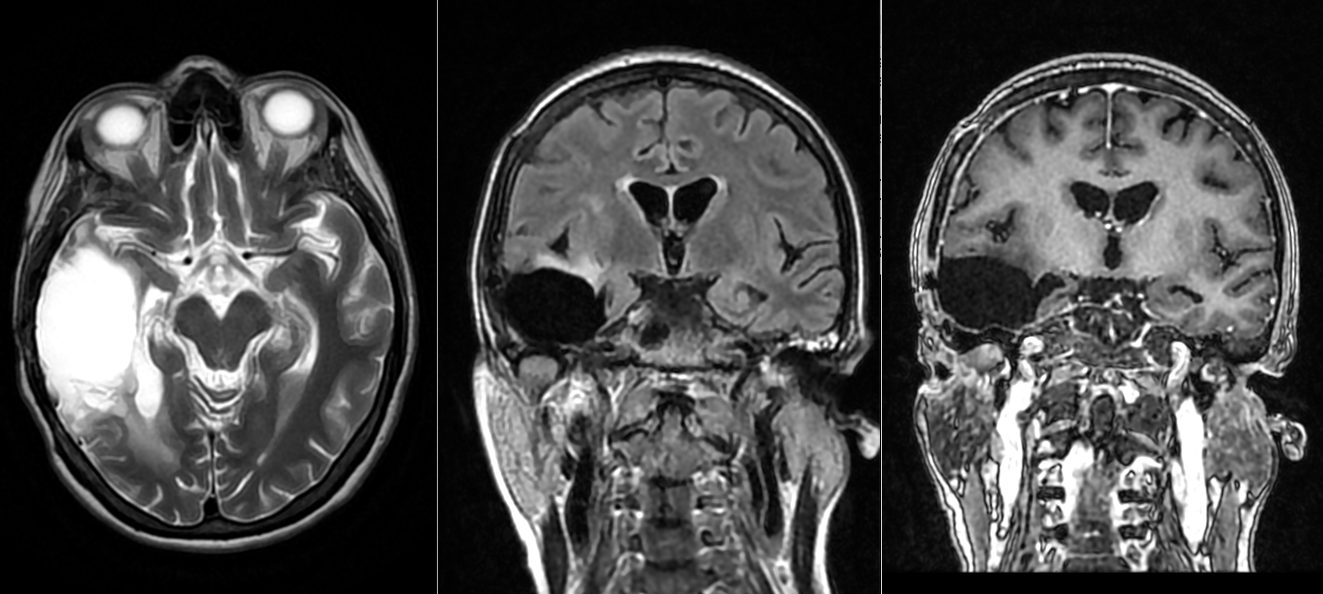

Astrocitom anaplazic grad III temporo-occipital drept – fără recidivă la 8 ani dupa operație

10. Evoluție și recidivă

Chiar și cu tratament optim, există un risc semnificativ de recidivă locală. În multe cazuri, recidiva se transformă într-un glioblastom secundar. De aceea, monitorizarea atentă este esențială.

Astrocitom grad III operat – progresie sub tratament